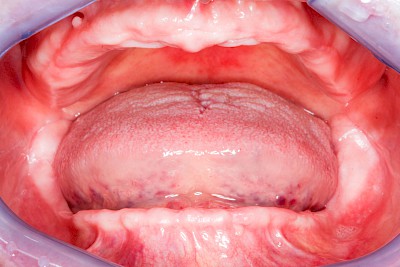

Überbeine im Bereich der Kiefer sind gar nicht so selten. Häufiger im Bereich der Seitenzähne unterhalb des Zahnfleisches, aber auch in der Mitte vom Gaumen. Überbeine haben in dem Sinne keinen Krankheitswert, müssen also nicht operativ entfernt werden, wenn diese nicht stören. Überbeine können ein Anzeichen für Knirschen und Pressen sein.